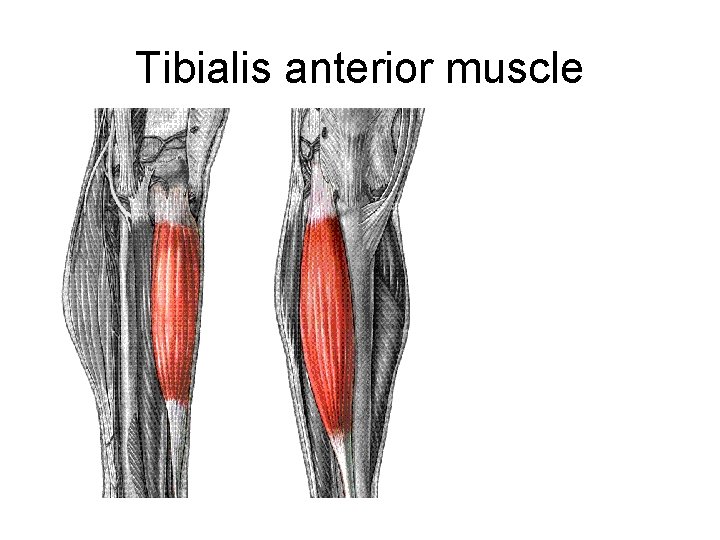

Tibialis anterior muscle